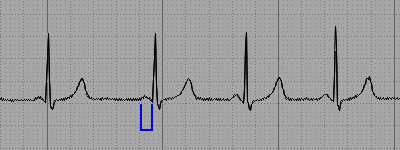

Normalnarrow QRS morphology in the presence of paroxysmal tachyarrhythmias. The Lown-Ganong-Levine LGL pattern is characterized by the presence of a short PR interval 120 milliseconds and normal QRS complex on the surface electrocardiogram ECG. El síndrome de Lown-Ganong-Levine es una enfermedad del corazón que se incluye en el grupo de trastornos denominados síndromes de pre-excitación cardiacaEstá producido por una conducción anómala por una vía eléctrica accesoria entre la aurícula y el ventrículoComparte muchas características con el síndrome de Wolff-Parkinson-White.

The Lown-Ganong-Levine LGL syndrome occurs when an accessory pathway is congenitally present that directly connects the atria to the ventricles bypassing the AV node similar to the Wolff. Characteristic ECG findings of short PR interval.

El síndrome de Lown-Ganong-Levine es una enfermedad del corazón que se incluye en el grupo de trastornos denominados síndromes de pre-excitación cardiacaEstá producido por una conducción anómala por una vía eléctrica accesoria entre la aurícula y el ventrículoComparte muchas características con el síndrome de Wolff-Parkinson-White. Lown Ganong Levine LGL syndrome is a rare short PR interval pre-excitation cardiac conduction abnormality characterised by episodes of. Lown-Ganong-Levine syndrome is a condition in which episodes of a fast heart rate tachycardia occur because of an abnormal electrical pathway in the heart. Early Repolarization ECG Example 1 Early Repolarization ECG Example 2 Lown-Ganong-Levine ECG Example 1 Lown-Ganong-Levine ECG Example 2 Prolonged QT Interval ECG. Characteristic ECG findings of short PR interval. What is Lown-Ganong-Levine syndrome. The Lown-Ganong-Levine LGL pattern was described in 1952 by Bernard Lown William Francis Ganong and Samual Levine and is theorized to involve an accessory pathway that partially or completely bypasses the atrioventricular AV node resulting in the direct activation of the bundle of His by the sinoatrial SA node. This finding may represent a perinodal accessory pathway or enhanced AV nodal conduction waveform 1. The Lown-Ganong-Levine LGL pattern is characterized by the presence of a short PR interval 120 milliseconds and normal QRS complex on the surface electrocardiogram ECG.